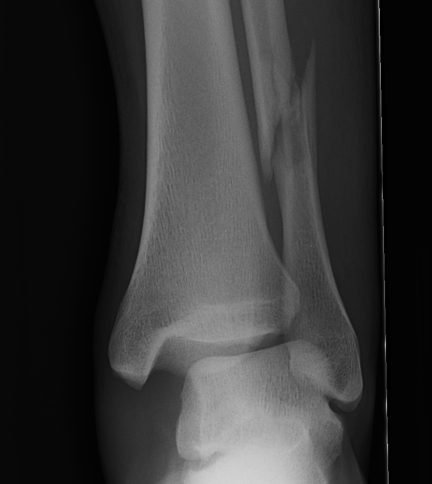

Ankle fractures are one of the more common injuries, and can vary in severity. Most commonly the fracture involves the fibula, although the distal tibia can also be injured. Xray is usually sufficient to diagnose these injuries.

Many fractures can be treated without surgery, if the fractures are in place anatomically and can be maintained in this position with a cast. When there is significant displacement, or indications that there is significant ligament injury, surgery is recommended.